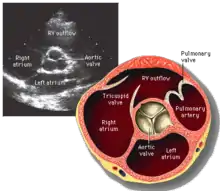

Parasternal short axis (PSAX)

This view is obtained in the same window as the parasternal long, but with the probe rotated 90°. In this view, the aortic valve is seen in cross-section with the right ventricular inflow & outflow tracts visible with the tricuspid valve as well. Pulmonary valve is not visible in this view. Both the right and left atria are visible.

The standard PSAX view is at the level of the aortic valve, but moving the probe along the long-axis can review the LV outflow tract, LV at the base, and LV at the midsection.

Structures visible:

- Aortic valve in short-axis

- Aortic valve dysfunction, aortic sclerosis/stenosis

- Tricuspid valve in long-axis

- Pulmonary valve in long-axis

- Right ventricle, including inflow and outflow tracts

- Left ventricle in short-axis

- Closer to the base can reveal the left ventricular outflow tract

- At the level of the base can show the movement of the mitral valve leaflets in short-axis

- At the level of mid-LV can show papillary muscles

Measurements in this view can be used to quantify the heart:

- Aortic valve area by planimetry

- Color doppler of all four valves

- Spectral doppler of tricuspid and pulmonary valves